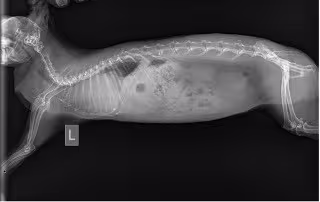

Рентгеновский снимок